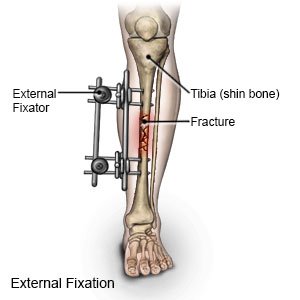

External Fixation

External fixation involves placing metal pins or screws into the bone on either side of the fracture and then connecting these pins with an external frame. This method is often used for complex or open fractures when there is a risk of infection, swelling, or when internal fixation isn't feasible.

External fixation is a process for fracture fixation by which pins or wires are inserted into bone percutaneously and held together via an external scaffold. Initially described by Malgaigne in 1853, external fixation was proposed as an alternative to immobilization in plaster cast, traction, or internal fixation.

External fixator types divide into several different subcategories, including uniplanar, multiplanar, unilateral, bilateral, and circular fixators. By adding pins in different planes (i.e., placed perpendicular to each other), one can create a multiplanar construct. Uniplanar fixation devices are fast and easy to apply but are not as sturdy as multiplanar fixation. Bilateral frames are created when the pins are on both sides of the bone and can also add additional stability.